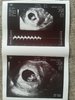

Pęcherzyk, 0,5 cm, wizyta serduszkowa 18 maja, termin porodu - wystrzałowy:31.12.2018. Dziewczyny, nie zapeszając, ale przypominam swoją historię wszystkim, którym ciężko- 1. podejście do ICSI, z 9 pobranych komórek 5 zapłodnionych, ale tylko 1 blastka transferowana 4AA, reszta nie przetrwała

. Trzymam mocno za wszystkie staraczki kciuki i życzę samych pozytywnych transferów. Oczywiście przed betą czułam się na maksa okresowo i nie wierzyłam, że przy 1 blastce się uda, a jednak nie warto tracić nadziei!